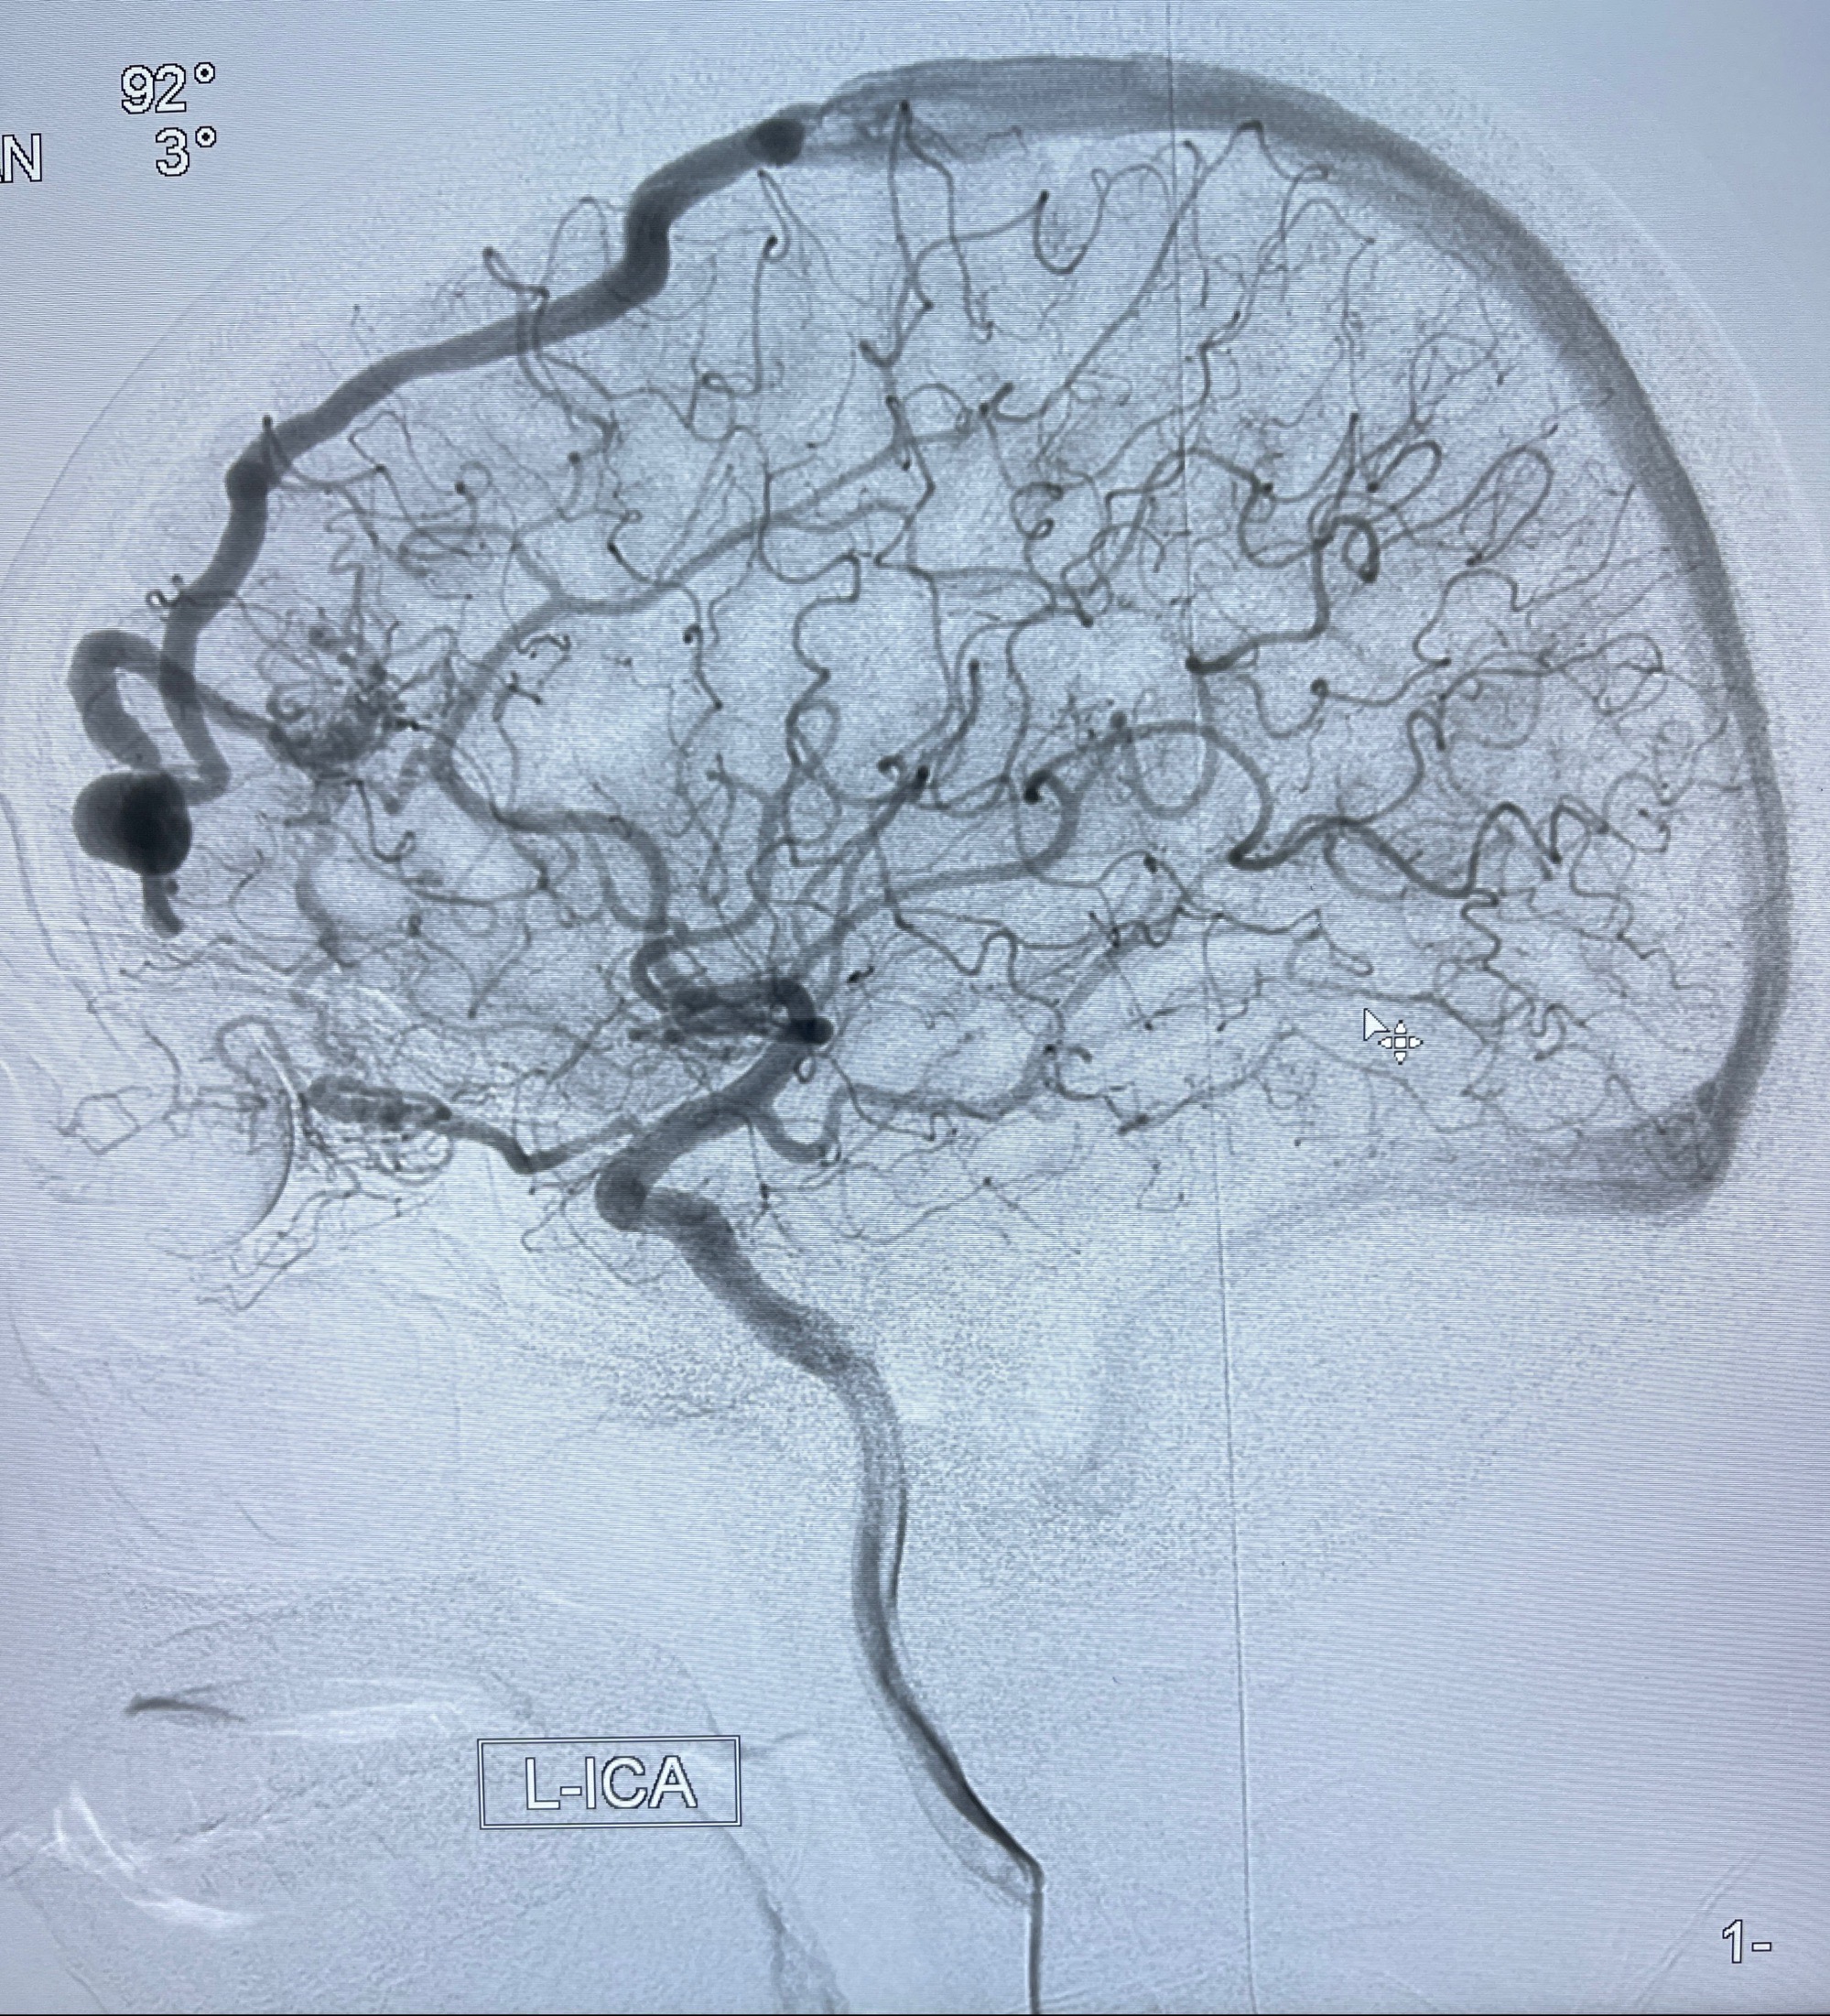

2023年8月21日]景德镇市第一人民医院脑血管造影检查,提示:主动脉弓、双侧颈总动脉、锁骨下动脉造影未见异常,左侧大脑前动脉静脉瘘。

2023-09-13全脑血管造影:前颅底硬脑膜动静脉瘘,供血动脉为双侧胼周动脉、眼动脉脑膜支,静脉向上矢状窦方向引流